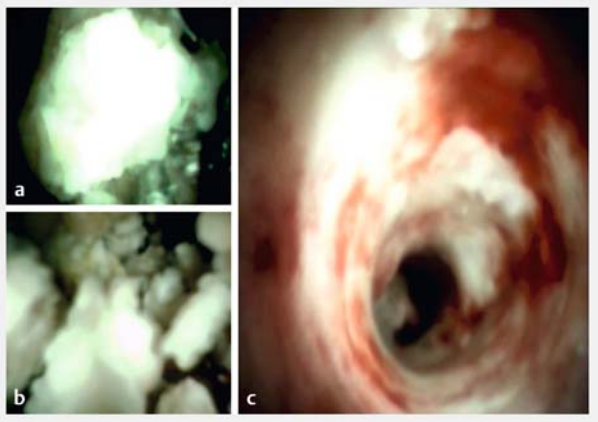

疼痛是慢性胰腺炎的主要症状,导致生活质量下降、失业率增加和主要医疗费用支出增加。镇痛药是胰腺疼痛治疗的基石。指南建议将内镜治疗和/或体外冲击波碎石术(ESWL)作为治疗胰头/胰体主胰管(MPD)阻塞的疼痛性无并发症慢性胰腺炎的一线疗法。数字化单人操作胰腺镜(DSOP)引导碎石术(图1)似乎是慢性胰腺炎合并PD扩张患者ESWL的的替代方案。

图 1. 数字化单人胰腺镜引导碎石术的示例图像显示:a 管腔内结石,碎石探头位于结石上;b 结石碎裂;c 清除结石碎片后管道完全畅通。